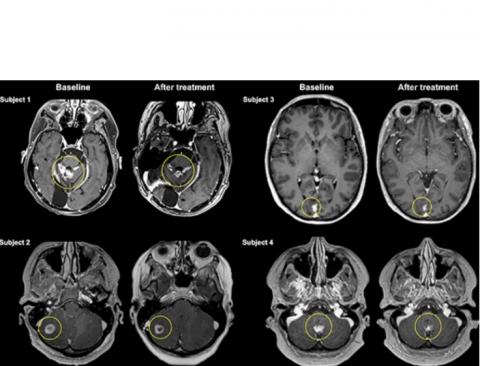

Il s’agit précisément de la publication de résultats préliminaires, chez 4 patientes de l’essai mené au total auprès de 10 participantes atteintes de cancer du sein métastatique, ou cancer du sein de stade IV, un type de cancer qui s’il prend naissance dans le sein s’est propagé au cerveau, aux os, au foie ou à d'autres organes. Les traitements actuels des métastases cérébrales du cancer du sein comprennent la neurochirurgie ouverte, la radiothérapie et la chimiothérapie. Cependant, la chirurgie et la radiothérapie sont souvent limitées par l'emplacement et le nombre de métastases cérébrales.

Ultrasons focalisés = plus d’efficacité : c’est la conclusion de cette analyse préliminaire, de l'efficacité du traitement, de l’évolution de la taille des tumeurs (soit une réduction moyenne de 21 %). Une réduction prometteuse de la taille des tumeurs mais qui doit encore être interprétée avec prudence dans l’attente de recherches supplémentaires.